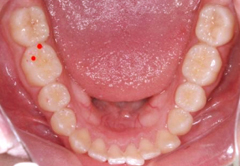

Los puntos rojos son las interferencias a la posición fisiológica de la mordida, una vez eliminados solo deben de quedar los puntos verdes que son los contactos correctos.